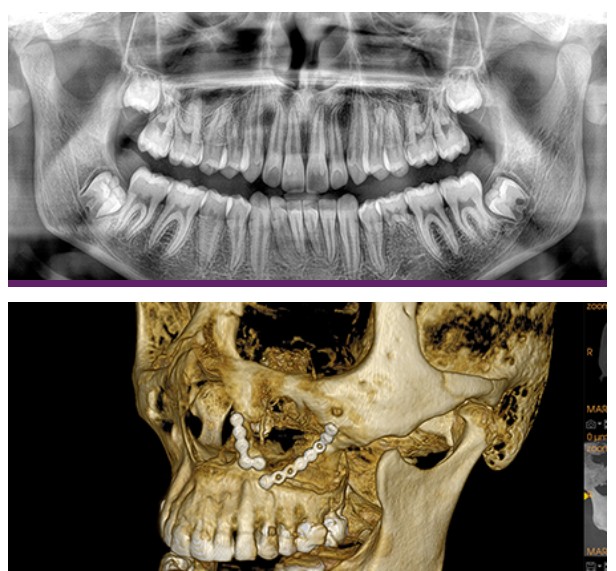

DEDICATED PANORAMIC

Thanks to its dedicated sensor technology, Carestream CS 9600 Premium captures low-dose traditional 2D panoramic X-ray images. Panoramic exam options include standard, segmented, TMJ (2 or 4 views), maxillary sinus and more.

LARGE FOV CONE BEAM

The CS 9600 Premium delivers a broad range of cone beam configurations and field of view sizes (i.e. 4x4, 5x5, 6x6, 10x5, 8x5, 8x8, 10x10, 12x5, 12x10, 16x12, 17x16 cm) to support a variety of applications, from endodontics and single implants to airway studies, and everything in between. For added patient safety, select the low-dose mode to capture high-quality scans at doses similar to standard 2D panoramic images.

HIGH RESOLUTION SCAN

With image resolution up to 90 μm, the CS 9600 Premium cone beam system delivers superior quality high-resolution 3D scans, providing the anatomical details required for exams and treatment requiring exact precision and accuracy.